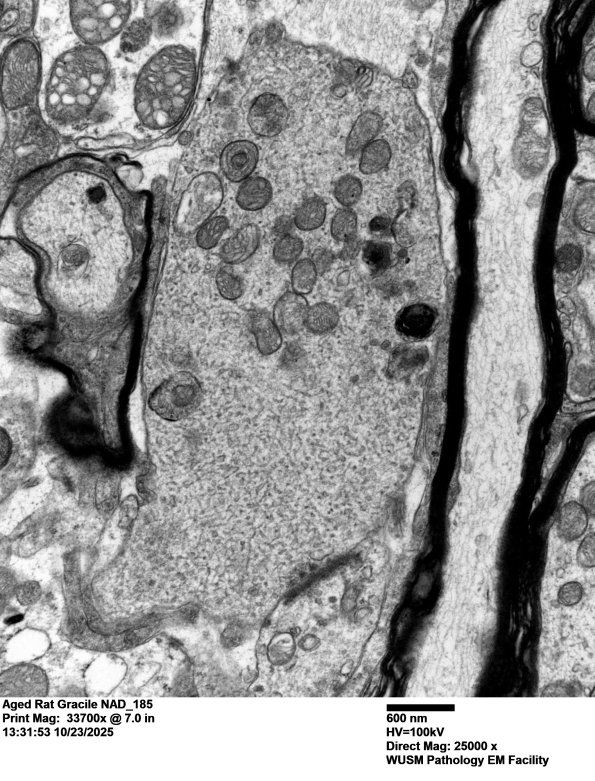

18Q1,2 A particularly photogenic dystrophic presynaptic axon containing tubulovesicular elements. (electron micrographs)